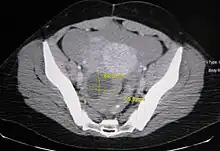

An Axial CT demonstrating a large hemorrhagic ovarian cyst. The cyst is delineated by the yellow bars with blood seen anteriorly.

Ovarian cysts are usually diagnosed by ultrasound, CT scan, or MRI, and correlated with clinical presentation and endocrinologic tests as appropriate.[10]